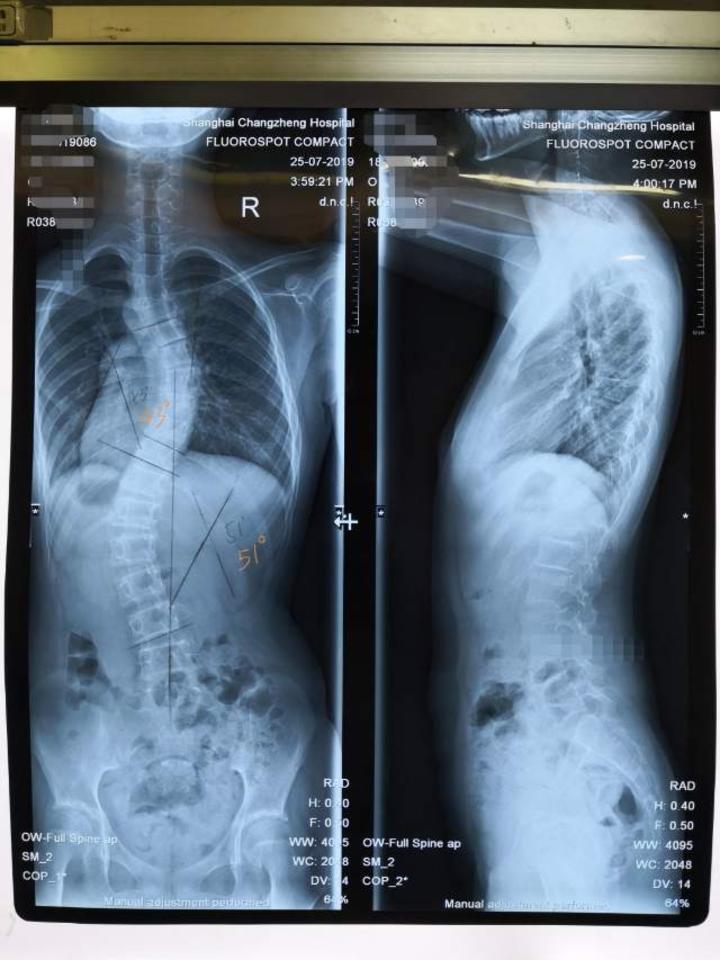

郑骨医,小儿骨科二脊柱侧弯科短阶段固定治疗脊柱侧弯一例

图片尺寸1734x2214